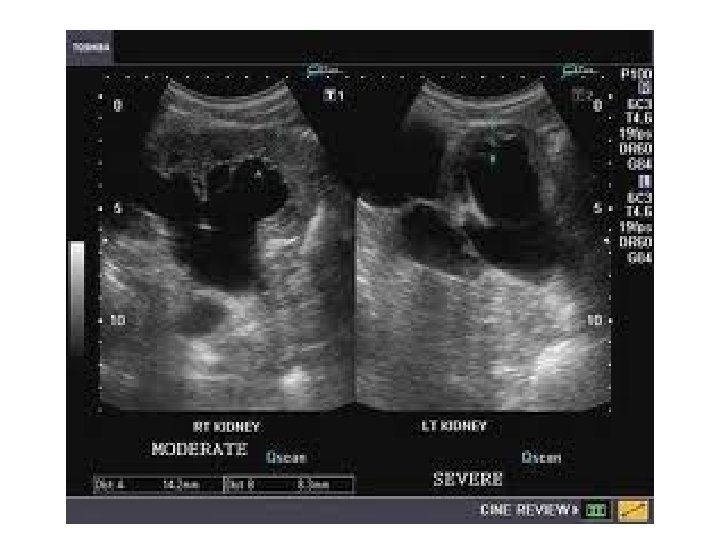

Case (4) • Young female presenting with decreased renal function (high urea and creatinine level).